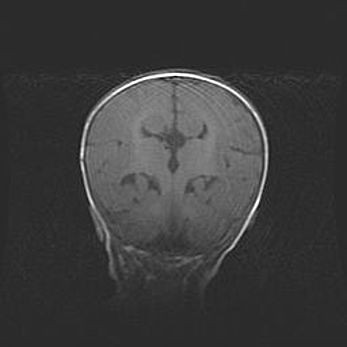

Наружная гидроцефалия с возможной атрофией височных областей.

Возраст: 28 дней

Вес: 3670 г

Пол: мужской

Окружность головы: 38 см

Срок гестации: 40 недель

Гидроцефалия головного мозга у новорожденных – это заболевание, которое характеризуется скоплением избыточного количества спинномозговой жидкости в желудочковой системе головного мозга в результате затруднения её перемещения от места выработки к месту поглощения в кровеносную систему или вследствие нарушения абсорбции. При открытой наружной форме гидроцефалии у новорожденных расширяются и переполняются субарахноидные пространства.

При нормотензивных  формах,  которые,  как  правило,  являются  следствием  перенесенных ишемических  повреждений  паренхимы  мозга,  возможно  сочетание микроцефалии  с нормотензивной гидроцефалией. В основе данных изменений лежит атрофия больших полушарий с преимущественной  локализацией  в  лобно-височных  областях.